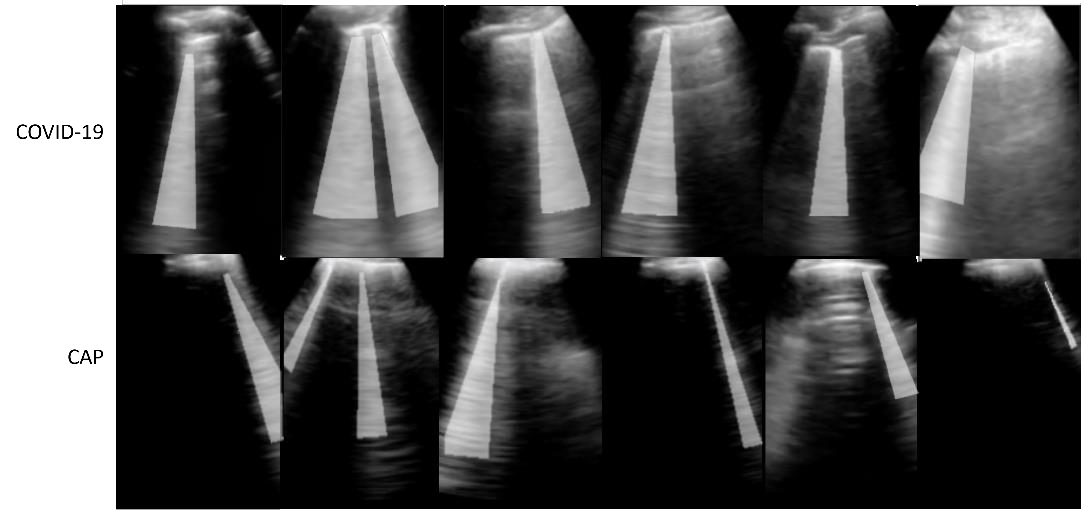

Lung ultrasound imaging has been shown effective in detecting typical patterns for interstitial pneumonia, as a point-of-care tool for both patients with COVID-19 and other community-acquired pneumonia (CAP). In this work, we focus on the hyperechoic B-line segmentation task. Using deep neural networks, we automatically outline the regions that are indicative of pathology-sensitive artifacts and their associated sonographic patterns. With a real-world data-scarce scenario, we investigate approaches to utilize both COVID-19 and CAP lung ultrasound data to train the networks; comparing fine-tuning and unsupervised domain adaptation. Segmenting either type of lung condition at inference may support a range of clinical applications during evolving epidemic stages, but also demonstrates value in resource-constrained clinical scenarios. Adapting real clinical data acquired from COVID-19 patients to those from CAP patients significantly improved Dice scores from 0.60 to 0.87 (p < 0.001) and from 0.43 to 0.71 (p < 0.001), on independent COVID-19 and CAP test cases, respectively. It is of practical value that the improvement was demonstrated with only a small amount of data in both training and adaptation data sets, a common constraint for deploying machine learning models in clinical practice. Interestingly, we also report that the inverse adaptation, from labelled CAP data to unlabeled COVID-19 data, did not demonstrate an improvement when tested on either condition. Furthermore, we offer a possible explanation that correlates the segmentation performance to label consistency and data domain diversity in this point-of-care lung ultrasound application.